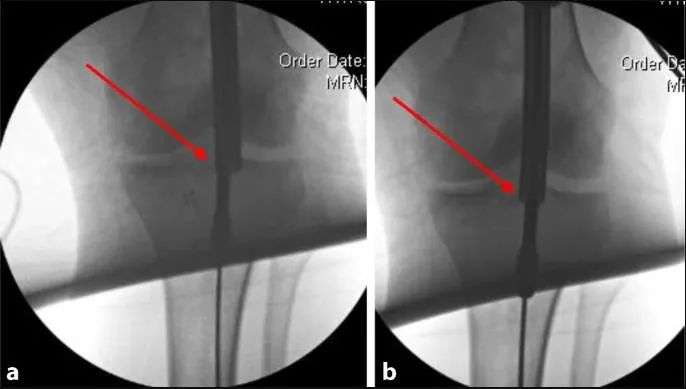

Однако в большинстве случаев для достижения и поддержания удовлетворительной репозиции этих переломов требуется некоторый редукционный маневр. Если линия перелома простая и изогнутая, можно использовать простые заостренные зажимы для возврата или коаптивные зажимы, устанавливаемые чрескожно, для достижения и поддержания возврата во время установки гвоздей. Если зажим неадекватен или плоскость перелома не поддается зажиму, пыльцовые или блокирующие винты могут помочь предотвратить смещение и неправильное положение (рис. 15). Эти винты размещаются позади желаемого положения гвоздя на виде сбоку и сбоку от желаемого положения стержня на виде спереди и сзади. Правильное размещение этих винтов для хорошего сброса может оказаться сложной задачей.

Рис. 15 Стопорные винты, расположенные снаружи желаемого пути гвоздя на видах спереди и сзади (а) и позади желаемого пути гвоздя на виде сбоку (б), противодействуют силам деформации